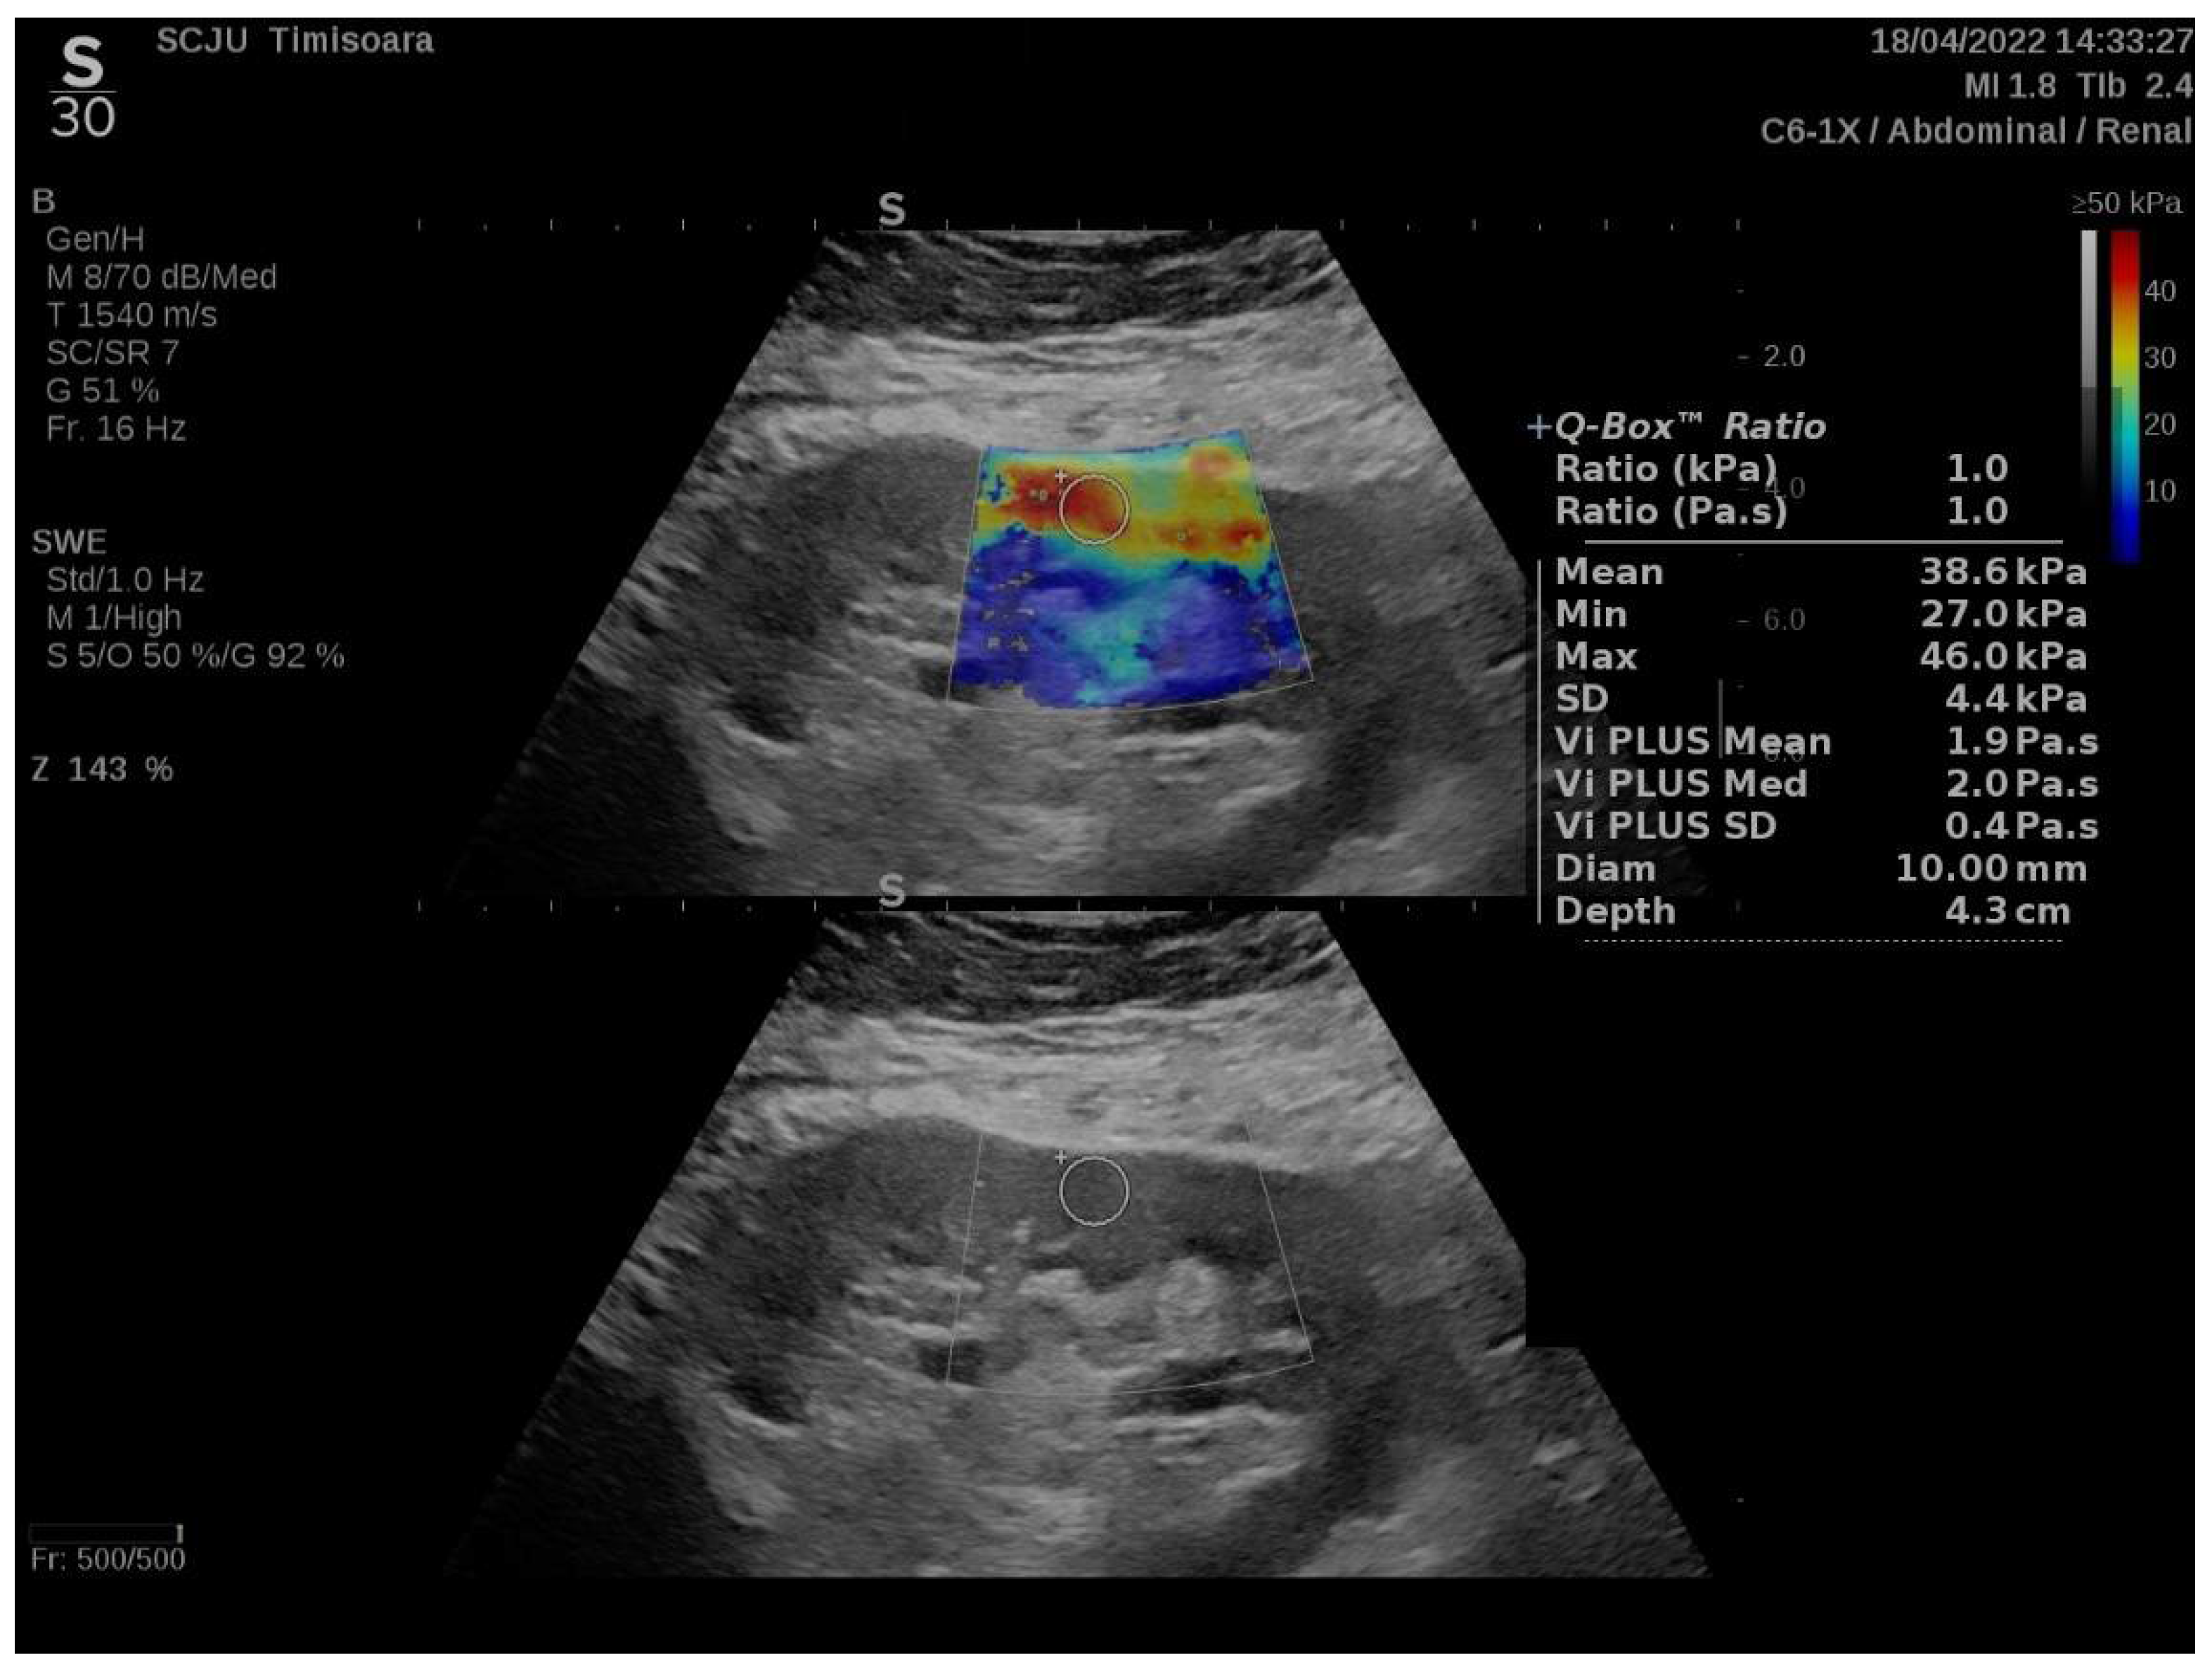

2.2. Elastography Using 2D-SWE PLUS and Vi PLUS